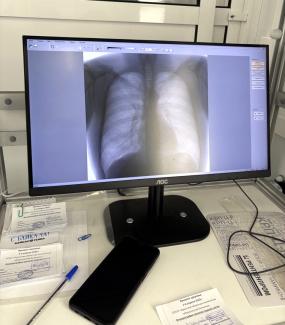

Врач-рентгенологи Марина Леонидовна Полохина и Елена Андреевна Гончарук в мобильном флюорографе Усольской городской больницы с помощью рентген-лаборанта Усольской ГБ Александра Мурашкина за три дня провели рентгенологические осмотры 346 человек

В общей сложности они обнаружили 4 случая пневмонии, одно подозрение на опухоль, по одному случаю фиброза и наличия кальцинатов. Посетителям рекомендовано обратиться к профильным специалистам для уточнения диагноза и лечения.